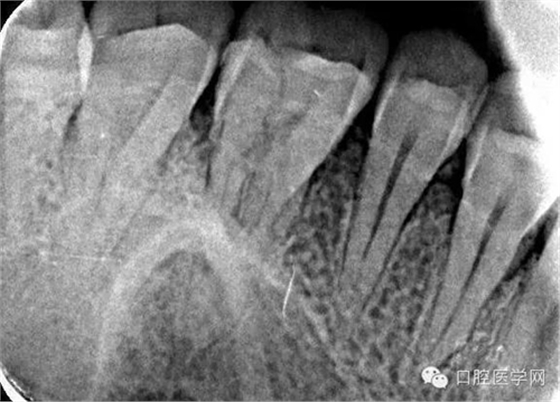

26根尖片可見低密度暗影: